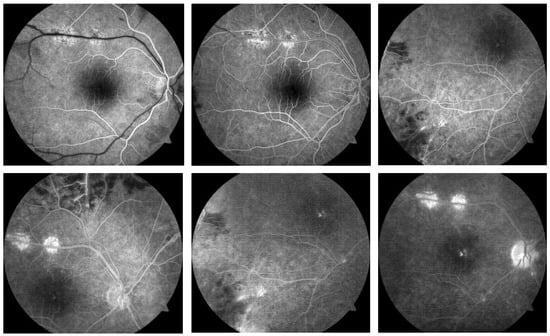

Fundus fluorescein angiography was performed for both eyes. The arterial phase revealed sharply demarcated areas of non-perfusion. The early venous phase revealed staining of inflamed veins, well-delineated areas of non-perfusion, and hyperfluorescence of the disc in the area of the newly formed retinal vessels. The late phase demonstrated leakage of the dye from new vessels, significant staining of the vessels, and macular leakage (Figure 3).

Figure 3. Fluorescein angiography of the right eye of a 34-year-old male with Eales disease. There were well-delineated areas of non-perfusion in the arterial phase. The early venous phase exhibited staining of the inflamed vessels, hyperfluorescence of the optic disc, and newly formed vessels. We observed leakage at the level of the new vessels and the macula, as well as staining of the vessels during the late phase.